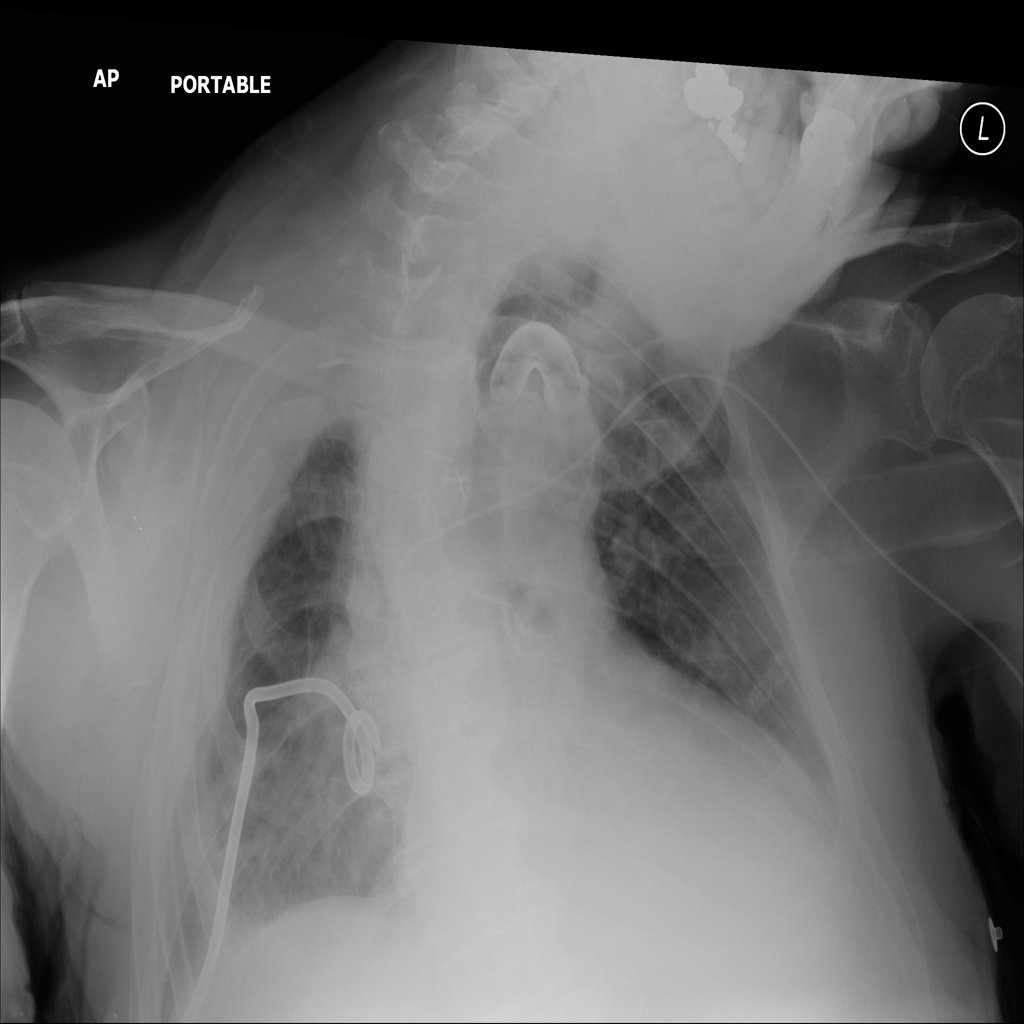

Mass

A mass is a larger focal opacity or lesion seen on the image. It is a descriptive finding that can have several causes and usually needs more imaging or clinical context to characterize.

PAT-E1D6 · IMG-034Mass

PAT-E1D6 · IMG-034

AP